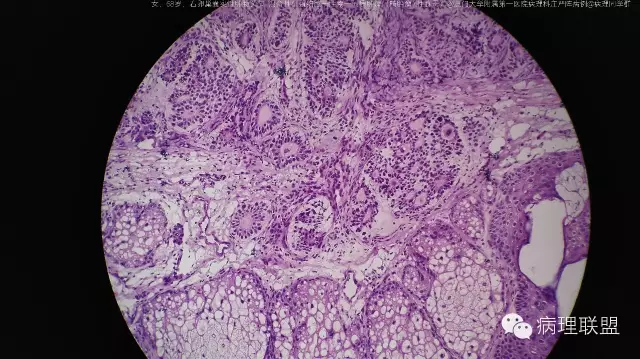

右卵巢囊实性肿物头节-混合性生殖细胞一性索一间质肿瘤(畸胎瘤+性腺母)